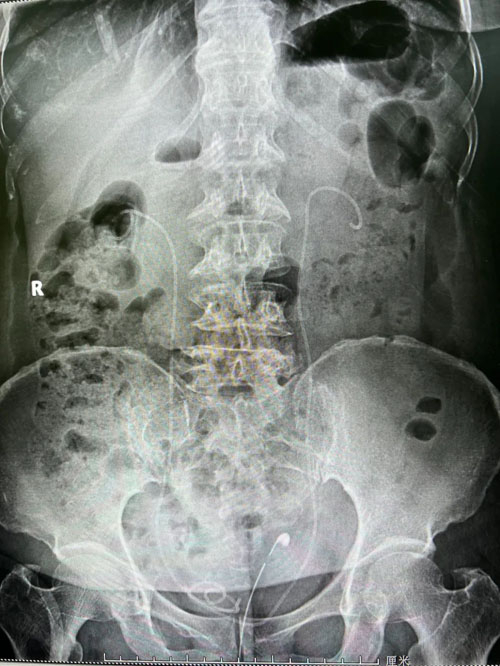

患者術(shù)前CT

在程廣舟副院長的指導(dǎo)下,程波副主任為患者實(shí)施手術(shù)。患者結(jié)石質(zhì)地堅(jiān)硬,碎石困難,在麻醉醫(yī)師與手術(shù)室護(hù)士的通力配合下,該患者順利完成雙側(cè)“無管化”經(jīng)皮腎鏡碎石取石術(shù)。從精準(zhǔn)穿刺到擴(kuò)張,再到手術(shù)結(jié)束,僅僅用了1個(gè)半小時(shí)。手術(shù)過程中,麻醉醫(yī)生密切觀察患者情況,術(shù)后患者順利復(fù)蘇,術(shù)后恢復(fù)良好,未出現(xiàn)發(fā)熱情況,術(shù)后復(fù)查腹部平片未見結(jié)石殘留,患者及家屬非常滿意。